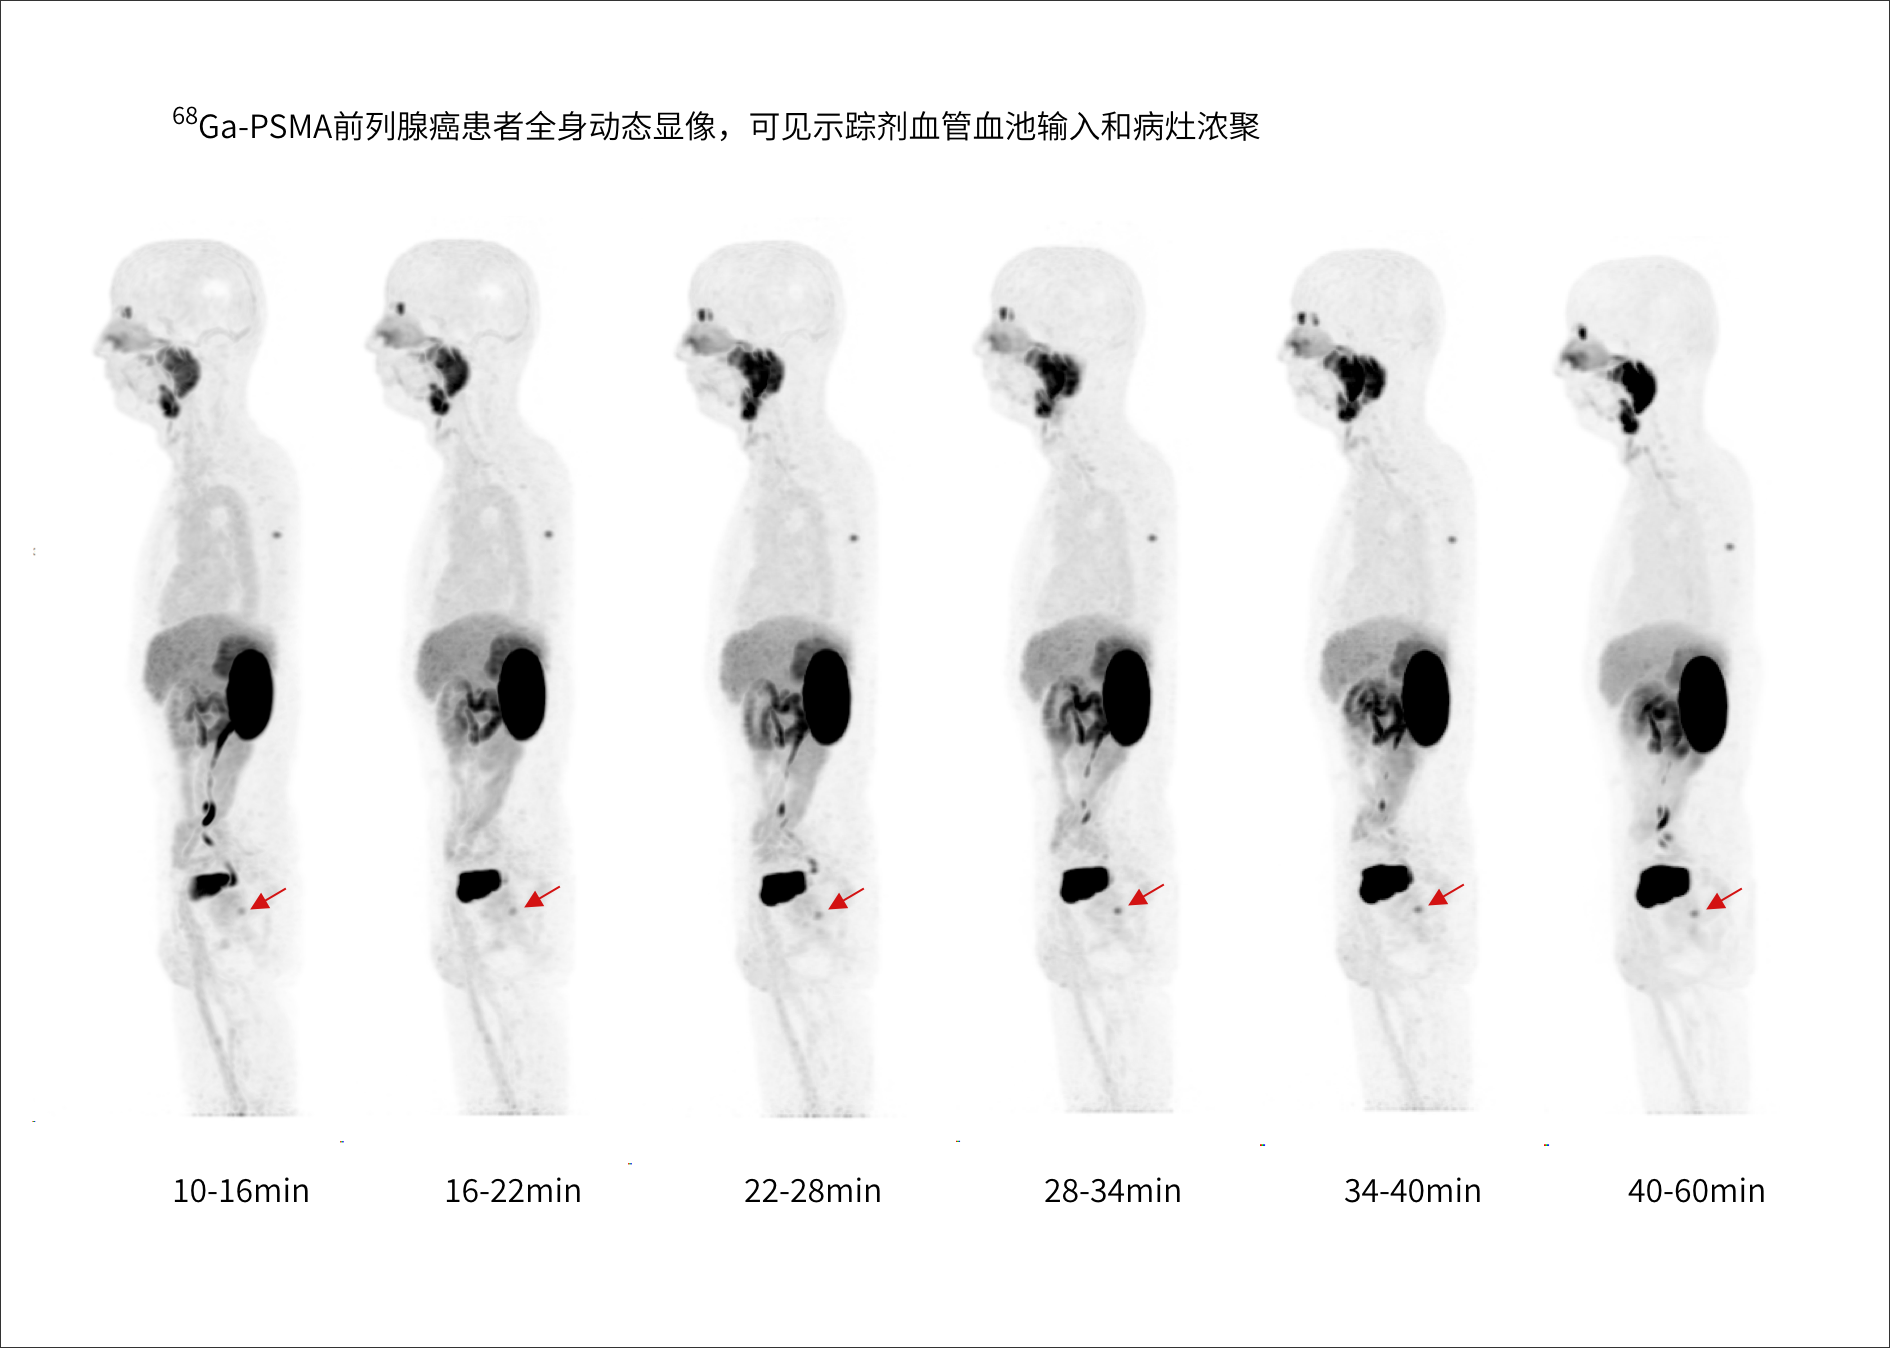

支持68Ga、 90Y、18F、82Rb、15O等不同半衰期、不同核素药物高清显像